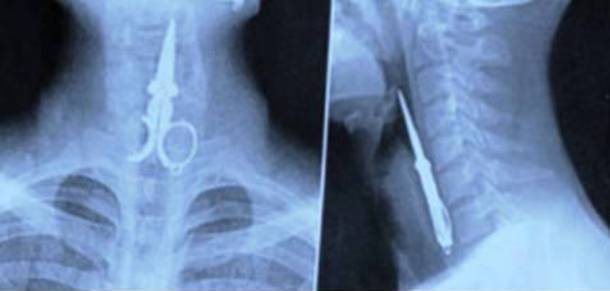

7. Nụ cười chết người

Trường hợp hy hữu này xảy ra khi một người Trung Quốc mượn kéo để... xỉa răng. Và trong khi đang xỉa răng thì bạn anh này lại vui tính kể chuyện cười, khiến anh này nuốt luôn phải chiếc kéo...